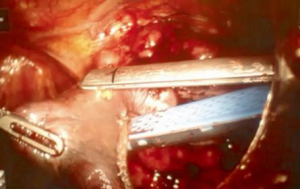

The side of surgical access was based on a single surgeon’s experience, or occasionally on the presence of unilateral tumor predominance. The surgical technique of robotic thymectomy from either the left or right side has been described in existing literature (15,16). This procedure was performed differently from thymectomy for non-thymomatous patients, with all surgeons adopting a “no-touch technique” for an “en bloc” resection of thymus and perithymic fat tissue. In this technique, the thymoma was never touched and the normal thymic tissue and peri-thymic fat were used for grasping and for traction. This technique avoids a direct manipulation of the tumor, in order to minimize the risk of tumor seeding in consequence of capsule damage. All thymus and perithymic fat were dissected with safe surgical margins, according to the International Thymic Malignancy Interest Group criteria (17), and the completeness of thymectomy was assessed by macroscopic inspection of the thymic bed, specimen and subsequent pathological analysis (Figure 2).

Since its introduction into clinical practice in the early 1990s, VATS has gained broad acceptance for diagnostic and therapeutic interventions for both pulmonary and mediastinal benign diseases (3-6). The main recognized advantages of VATS compared with open approaches are minimal operative trauma, lower morbidity, early improved pulmonary function, shorter hospital stays and better cosmetic results (3,4,18). These obvious advantages have increased the acceptability of the VATS approach, especially among patients with MG, leading to an increased number of thoracoscopic thymectomies being performed for non-thymomatous MG with good surgical and neurological results (15,16,19). Contrary to the lung cancer experience however, in which VATS resection has become the standard approach for early-stage NSCLC, most surgeons are still reluctant to perform a thoracoscopic thymectomy in patients with thymoma, due to technical and oncological concerns. There are a number of technical reasons to not use thoracoscopy: the upper mediastinum is a delicate and difficult-to-reach anatomical area with vulnerable large vessels and nerves, particularly with thoracoscopy. In the two-dimensional view of the operative field, the surgeon’s tremor is enhanced by the thoracoscopic instruments and they do not articulate, making it difficult to operate in a fixed three-dimensional space such as the mediastinum. Moreover, thoracoscopic thymectomy is considered a technically challenging operation with a steep learning curve (10). The oncological concerns relate to the possible breach of tumor capsule with risk of tumor seeding locally or in the pleural cavity, and the difficult evaluation of resection margins with reduced oncological accuracy and safety. The robotic surgical system has provided several advantages able to overcome some technical and methodological limits of conventional thoracoscopy: (I) the improved dexterity of instruments (7 degrees of freedom articulation, 360 degrees of rotation) allows complex three-dimensional movements, providing a safe and comfortable dissection around vessels, nerves, and tiny and remote areas such as the superior horns or the contralateral mediastinum; (II) the high-resolution, three-dimensional vision permits the best possible and magnified view of the surgical field; and (III) the filtering of hand tremors allows greater technical precision. In our opinion, these characteristics have significantly increased the safety and the oncological effectiveness of robotic thymectomy for thymoma. In fact, there is less manipulation of the thymic and perithymic tissue during the operation, and a better evaluation of healthy tissue as a result of the high quality image. This allows for a more precise and low-risk dissection with wide safety margins, and reduced possibility of an incautious tumor breaching, incomplete resection or iatrogenic injury. The lack of tactile feedback could theoretically increase the risk of damaging tumor capsule; however, this disadvantage seems widely compensated by the superior three-dimensional vision control of the system. In the last 15 years, several authors have published the results of thoracoscopic and robotic thymectomy for early-stage thymoma (Table 1). The available data confirm that this approach may be considered technically sound and safe in the hands of appropriately-trained surgeons. However, data are still inconclusive with regard to oncological outcome due to the lack of long-term follow-up. In fact, thymomas are indolent tumors, and a long lapse of time (at least 10 years) is necessary to evaluate the survival and relapse rate. Therefore, as pointed out by Davenport et al. in a systematic review (30), there is a lack of evidence in the current literature supporting a minimally invasive approach compared to a standard transsternal approach. At that time, the open transsternal surgical approach is widely considered the gold standard for resection of thymoma, ensuring the best chance for a complete resection (1,2). However, despite the lack of long oncological follow-up, the surgical results are outstanding: no major complications or mortality occurred in this large series. Other authors adopting either the conventional VATS or robotic approach also reported similar results (2,3,7-9,20,22-29). In contrast to other authors supporting a thoracoscopic subtotal thymectomy for non-invasive thymoma without MG as the preferred resection modality regardless of tumor size and tumor capsule characteristics (2,8-19,30,31), our policy was to undertake an extended thymectomy in all cases, such as in the open approach. In the absence of definitive long-term data, a standardization of the technique is necessary in order to avoid biases in the evaluation of the outcome. Moreover, we consider the intraoperative manipulation of the specimen to be safer when the perithymic fat tissue is contextually resected ‘en bloc’. Most of our patients (87.3%) had an early-stage tumor due to the selection criteria we adopted, based on the radiological criteria proposed by Cheng et al. (7): the location in the anterior mediastinum, tumor encapsulation, a distinct fat plane between the thymoma and vital organs, the existence of residual normal appearing thymic tissue, no mass compression effect and unilateral tumor predominance, particularly for tumors of dimension greater than 3 cm. However, while most cases were clinically diagnosed as Masaoka stage I, 52.9% patients were found to be Masaoka stage II, 8.3% were in stage III and 4.4% in stage IVa/b after resection and final histological evaluation. A similar finding was reported by Takeo et al. (21), where it was revealed that 57% of patients had Masaoka stage II and III after an initial clinical diagnosis of stage I, while in a report by Quintanilla-Martinez et al. (32), 28.5% of the tumor reported by the surgeon to be encapsulated showed a microscopic evidence of capsular invasion. In regards to Masaoka stage III and IV discovered at surgical exploration, our policy was to convert to an open access (sternotomy or thoracotomy) based on individual surgeon’s judgement. In particular, when the resection was considered unsafe or unfeasible by robotic approach, an open resection was performed; this occurred in 10 cases, while in the remaining seven cases, a resection extending to the pericardium, the phrenic nerve (Figure 3), lung (Figure 4) or parietal pleura were performed entirely by robotics. Despite being technically feasible, extended resections should be considered experimental and reserved to very select cases, as the oncological safety is still unknown. Another debated point is the appropriate size of thymoma for VATS or robotic resection; the majority of authors dealt with lesions smaller than 5 cm, but an average tumor diameter around 3 cm is generally considered as oncologically acceptable (10,27). In our experience, the mean diameter of resected lesions was 4.4 cm, with a range between 1 and 10 cm. A large tumor size was not considered an absolute contraindication; however it may interfere with the surgical procedure, making the manipulation more difficult with increased chance of an open conversion, prolonged operative time or capsule injury, as reported by Kimura et al. (22). In regards to the surgical results, no mortality, low morbidity and short hospital stay were observed. The operative times and open conversion rate were comparable with other series of thoracoscopic thymoma resection (Table 1). It is interesting to note that no conversions due to intraoperative vascular accidents were required, as the accurate vision allowed the surgeons to perform an optimal vascular dissection or identify early vascular invasion, avoiding any intraoperative damage. Looking at the oncologic outcome, a recurrence rate ranging between 0% and 6.7% has been reported in previous thoracoscopic and robotic series. In our experience, the single pleural relapse was observed in a Masaoka stage IVa despite a macroscopic radical intervention. Relapses also frequently occur in open surgery due to microscopic residual disease. Cheng et al. (33) and Pennathur et al. (20) compared the VATS and transsternal approaches for thymoma in small series, reporting no significant difference in recurrence rate and overall survival between the two groups. Although very encouraging, the oncological results need definitive validation, since the indolent nature of thymoma requires more mature data from longer follow-up. The present study has some limitations, particularly the non-randomized, retrospective and multi-institutional methodology. In addition, the follow-up period is still inadequate to allow a definitive conclusion on the oncological outcome.